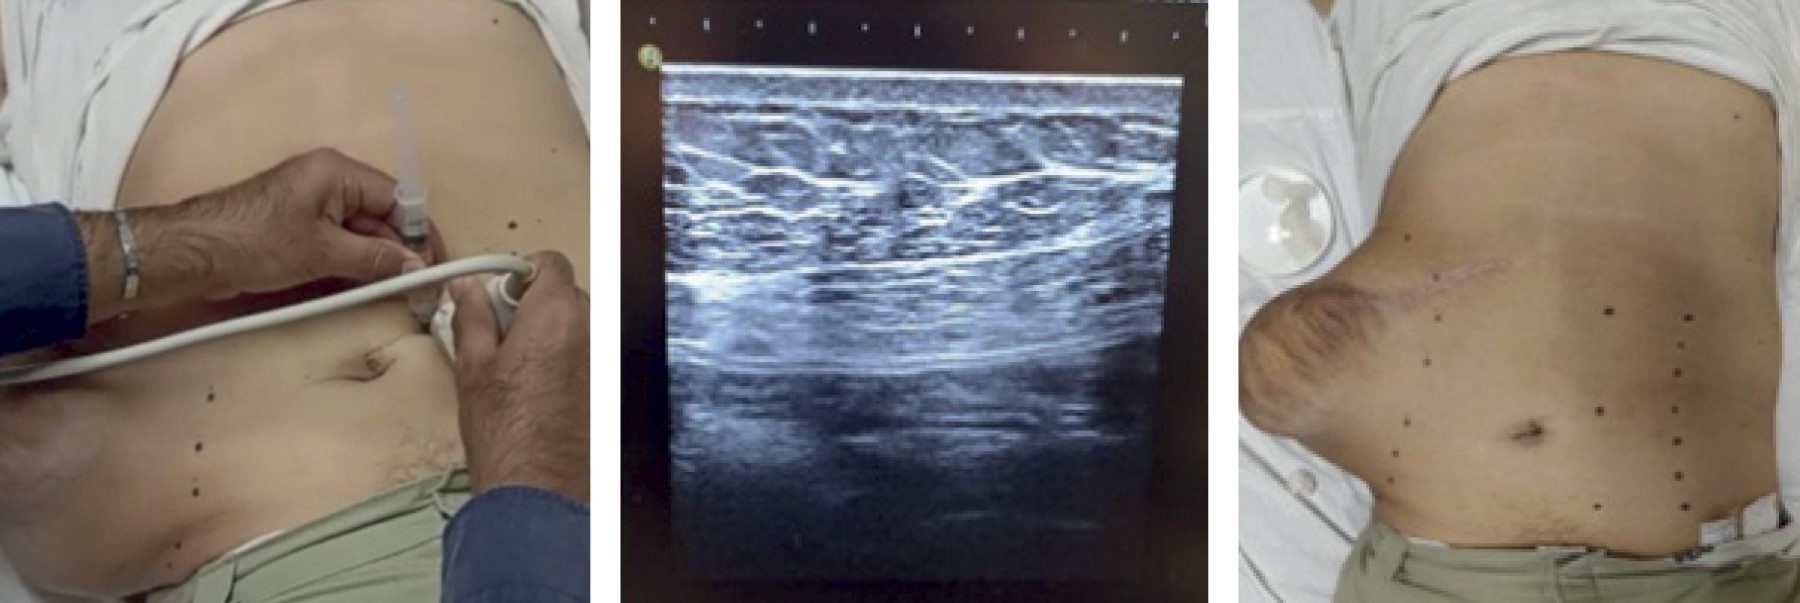

Caso 5. Hombre de 64 años, con antecedentes crónico-degenerativos positivos para hipertensión arterial y diabetes mellitus. Antecedentes quirúrgicos positivos para colecistectomía convencional con incisión tipo Kocher hacía 3 años, la cual presentó dehiscencia de herida. Dicha complicación fue tratada con curaciones y antibioticoterapia con una adecuada evolución, planeando realizar un cierre por tercera intención. Tres meses después del cierre comenzó con aumento de volumen progresivo en la región incisional (Figura 2), que no presentaba dolor; por lo que acudió al servicio de urgencias donde se le realizó tomografía axial simple de abdomen, en la cual se encontró defecto herniario en la región incisional de 30 mm de diámetro, con un saco herniario en la región incisional de 85 × 52 mm, contenido de asas intestinales sin mostrar datos de encarcelamiento, con un aumento del defecto en tres meses a 14 × 17 cm, lo que retrasó su tratamiento por motivos de la pandemia COVID-19. El defecto tuvo un incremento hasta llegar a 20 cm en su diámetro más amplio, mostrando aproximadamente 45% de su contenido intraabdominal. Se sometió a protocolo preoperatorio con aplicación de toxina botulínica Dysport tipo A (500 UI), con aplicación de neumoperitoneo progresivo (3,500 mL), en donde se encontró una reducción aproximada de 10 cm del saco herniario en comparación a las medidas previas al protocolo. Se realizó plastia con malla PROCEED de 30 × 30 intraperitoneal y técnica de separación de componentes (Figura 3). No tuvo complicaciones postquirúrgicas y egresó a su domicilio a los dos días del evento quirúrgico.

Figura 2

Figura 3